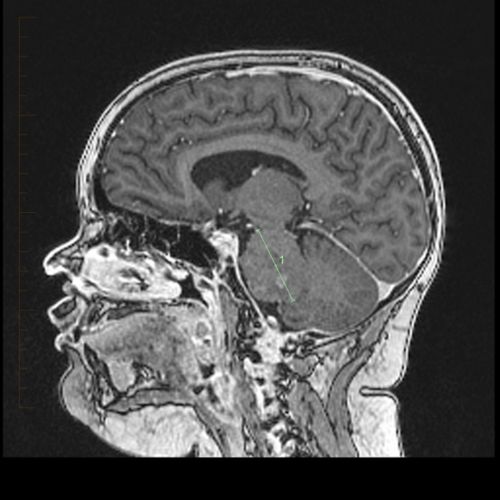

Many different types of brain tumors exist.

A brain tumor is a mass or growth of abnormal cells in your brain. Weakness in an arm or leg.